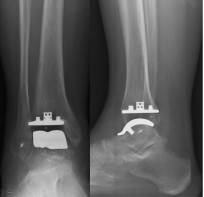

对于保守治疗无效且病情严重的患者,可能需要考虑手术治疗。手术方法包括关节镜手术清理关节腔、踝关节融合、踝关节置换等。